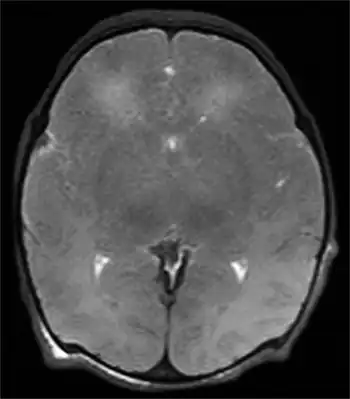

Multiple cerebral ischemic events may lead to subcortical ischemic depression, also known as vascular depression. This condition is most commonly seen in elderly depressed patients. Late onset depression is increasingly seen as a distinct sub-type of depression, and can be detected with an MRI.[11]